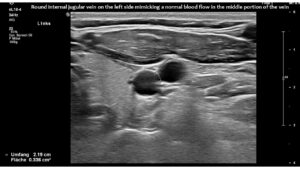

However, in this patient, both jugular veins were compressed. The middle portion of the internal jugular vein was pushed ventrally by the increased cervical lordosis on both sides, becoming squeezed between the carotid artery and the sternocleidomastoid muscle.

Consequently, blood had difficulty leaving the skull, resulting in continuously increased pressure and severe headaches, as well as other neurological dysfunction. The left side was more affected due to the double compression. This was clearly demonstrated by four-dimensional volume flow measurements in both jugular veins.